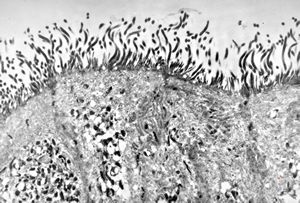

F,52y. | spirochetosis - colon